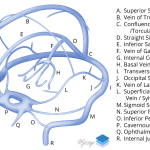

- Abnormal hyperdensity in the internal cerebral veins, the vein of Galen, and likely in portions of the thalamostriate veins